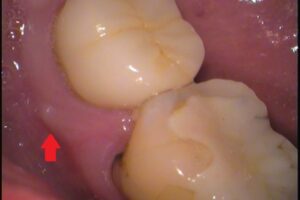

お口の中を見てみると、

歯ぐきにできものがあります。

その場所の歯はセラミックのかぶせ物がされており、以前に神経を抜いた歯です。歯の直下にできた、小さい腫れたできものができた場合、ほとんどが歯の根の先に膿がたまっているのが原因です。